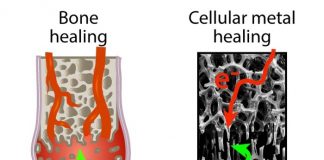

“코로나 후유증 세로토닌 고갈과 관련 있다”

신종 코로나바이러스 감염증 후유증 '롱 코로나'(Long COVID)가 세로토닌..